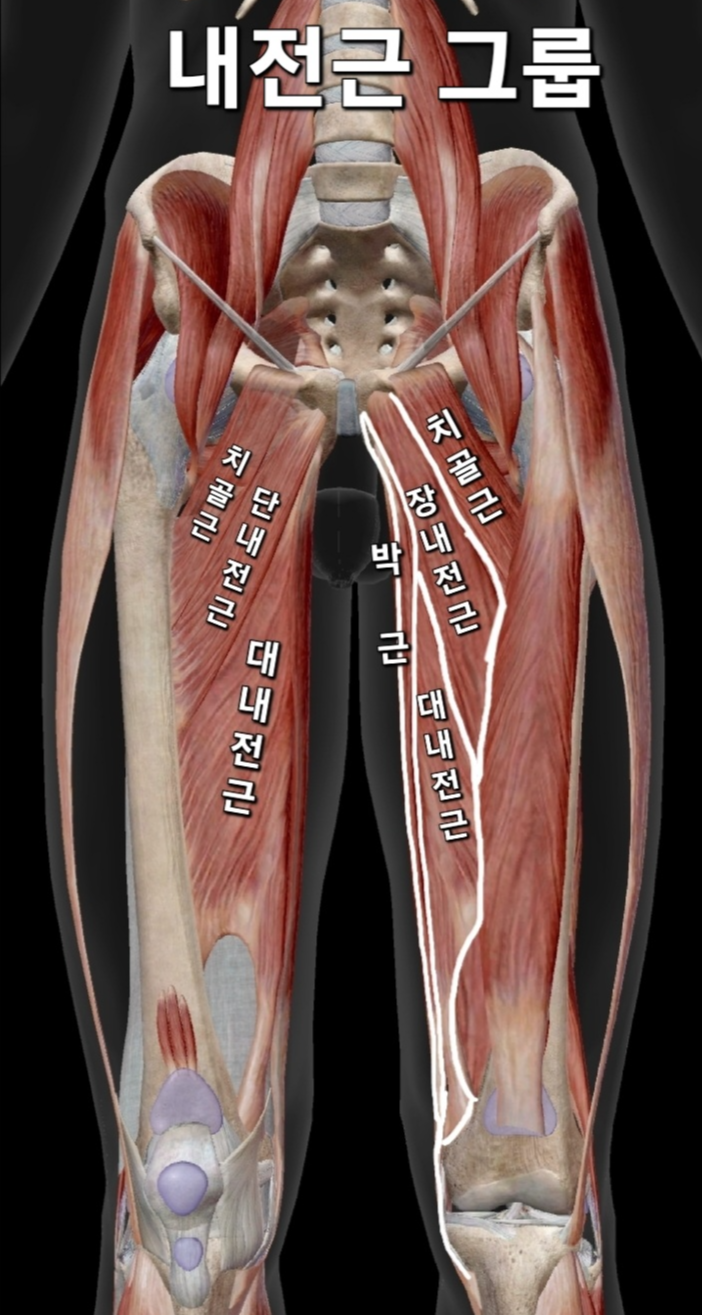

앞쪽 사타구니 통증 & 대퇴부 내측 집중통증

이유: 내전근(허벅지 안쪽 근육) 경직, 고관절 가동 범위 부족

ㆍ 내전근이 경직되면 대퇴골이 안으로 말리면서 충돌은 앞쪽에서 발생하게되고 양반다리할때 허벅지 안쪽통증이 발생됩니다고관절이 안으로 돌아가면(내회전), 대퇴골두(허벅지 뼈 머리 부분)와 비구(골반의 소켓 부분)가 부딪히면서 고관절 앞쪽에서 충돌(고관절 충돌 증후군)이 발생할 가능성이 커집니다 이때 양반다리 골반통증이 사타구니(고관절 앞쪽)에서 통증이 나타날 수 있습니다 특히 고관절을 구부릴 때(앉거나 몸을 숙일 때) 더 심한 통증이 나타날 수 있습니다

ㆍ내전근이 과도하게 긴장되면, 근육이 붙어 있는 치골 부위도 당겨지면서 통증이 생길 수 있습니다 특히 "치골지 골막염(Pubic Ramus Periostitis)" 같은 문제로도 발전할 수도 있습니다 그러면서 양반다리 골반통증이 생식기 주변 가까운 사타구니 쪽으로 집중적인 통증이 나타나게 됩니다 이 통증은 고관절을 안쪽으로 모으거나, 다리를 벌리는 동작에서 심해질 가능성이 큽니다

그래서 만약 양반다리할때 허벅지 안쪽통증이 발생으로 사타구니가 아프다면 고관절 충돌 증후군 때문일 가능성이 높고, 생식기 주변 가까운 사타구니 쪽만 아프다면 내전근 과긴장 문제일 가능성이 큽니다

관련 문제 : 고관절 구축 / 대퇴골-골반 불균형(Femur-Pelvis Imbalance)

ㆍ 고관절 구축은 고관절이 뻣뻣해져서 특정 방향으로 움직이는 게 제한되는 것입니다

ㆍ대퇴골-골반 불균형(Femur-Pelvis Imbalance)은 허벅지뼈와 골반의 정렬이 어긋나면서 불균형이 생긴 상태를 말합니다